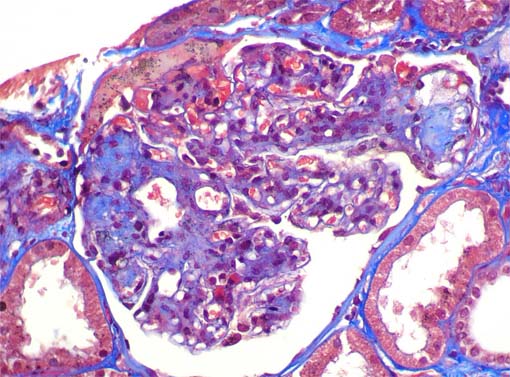

Figura 7.

Tricrómico de Masson, X400.